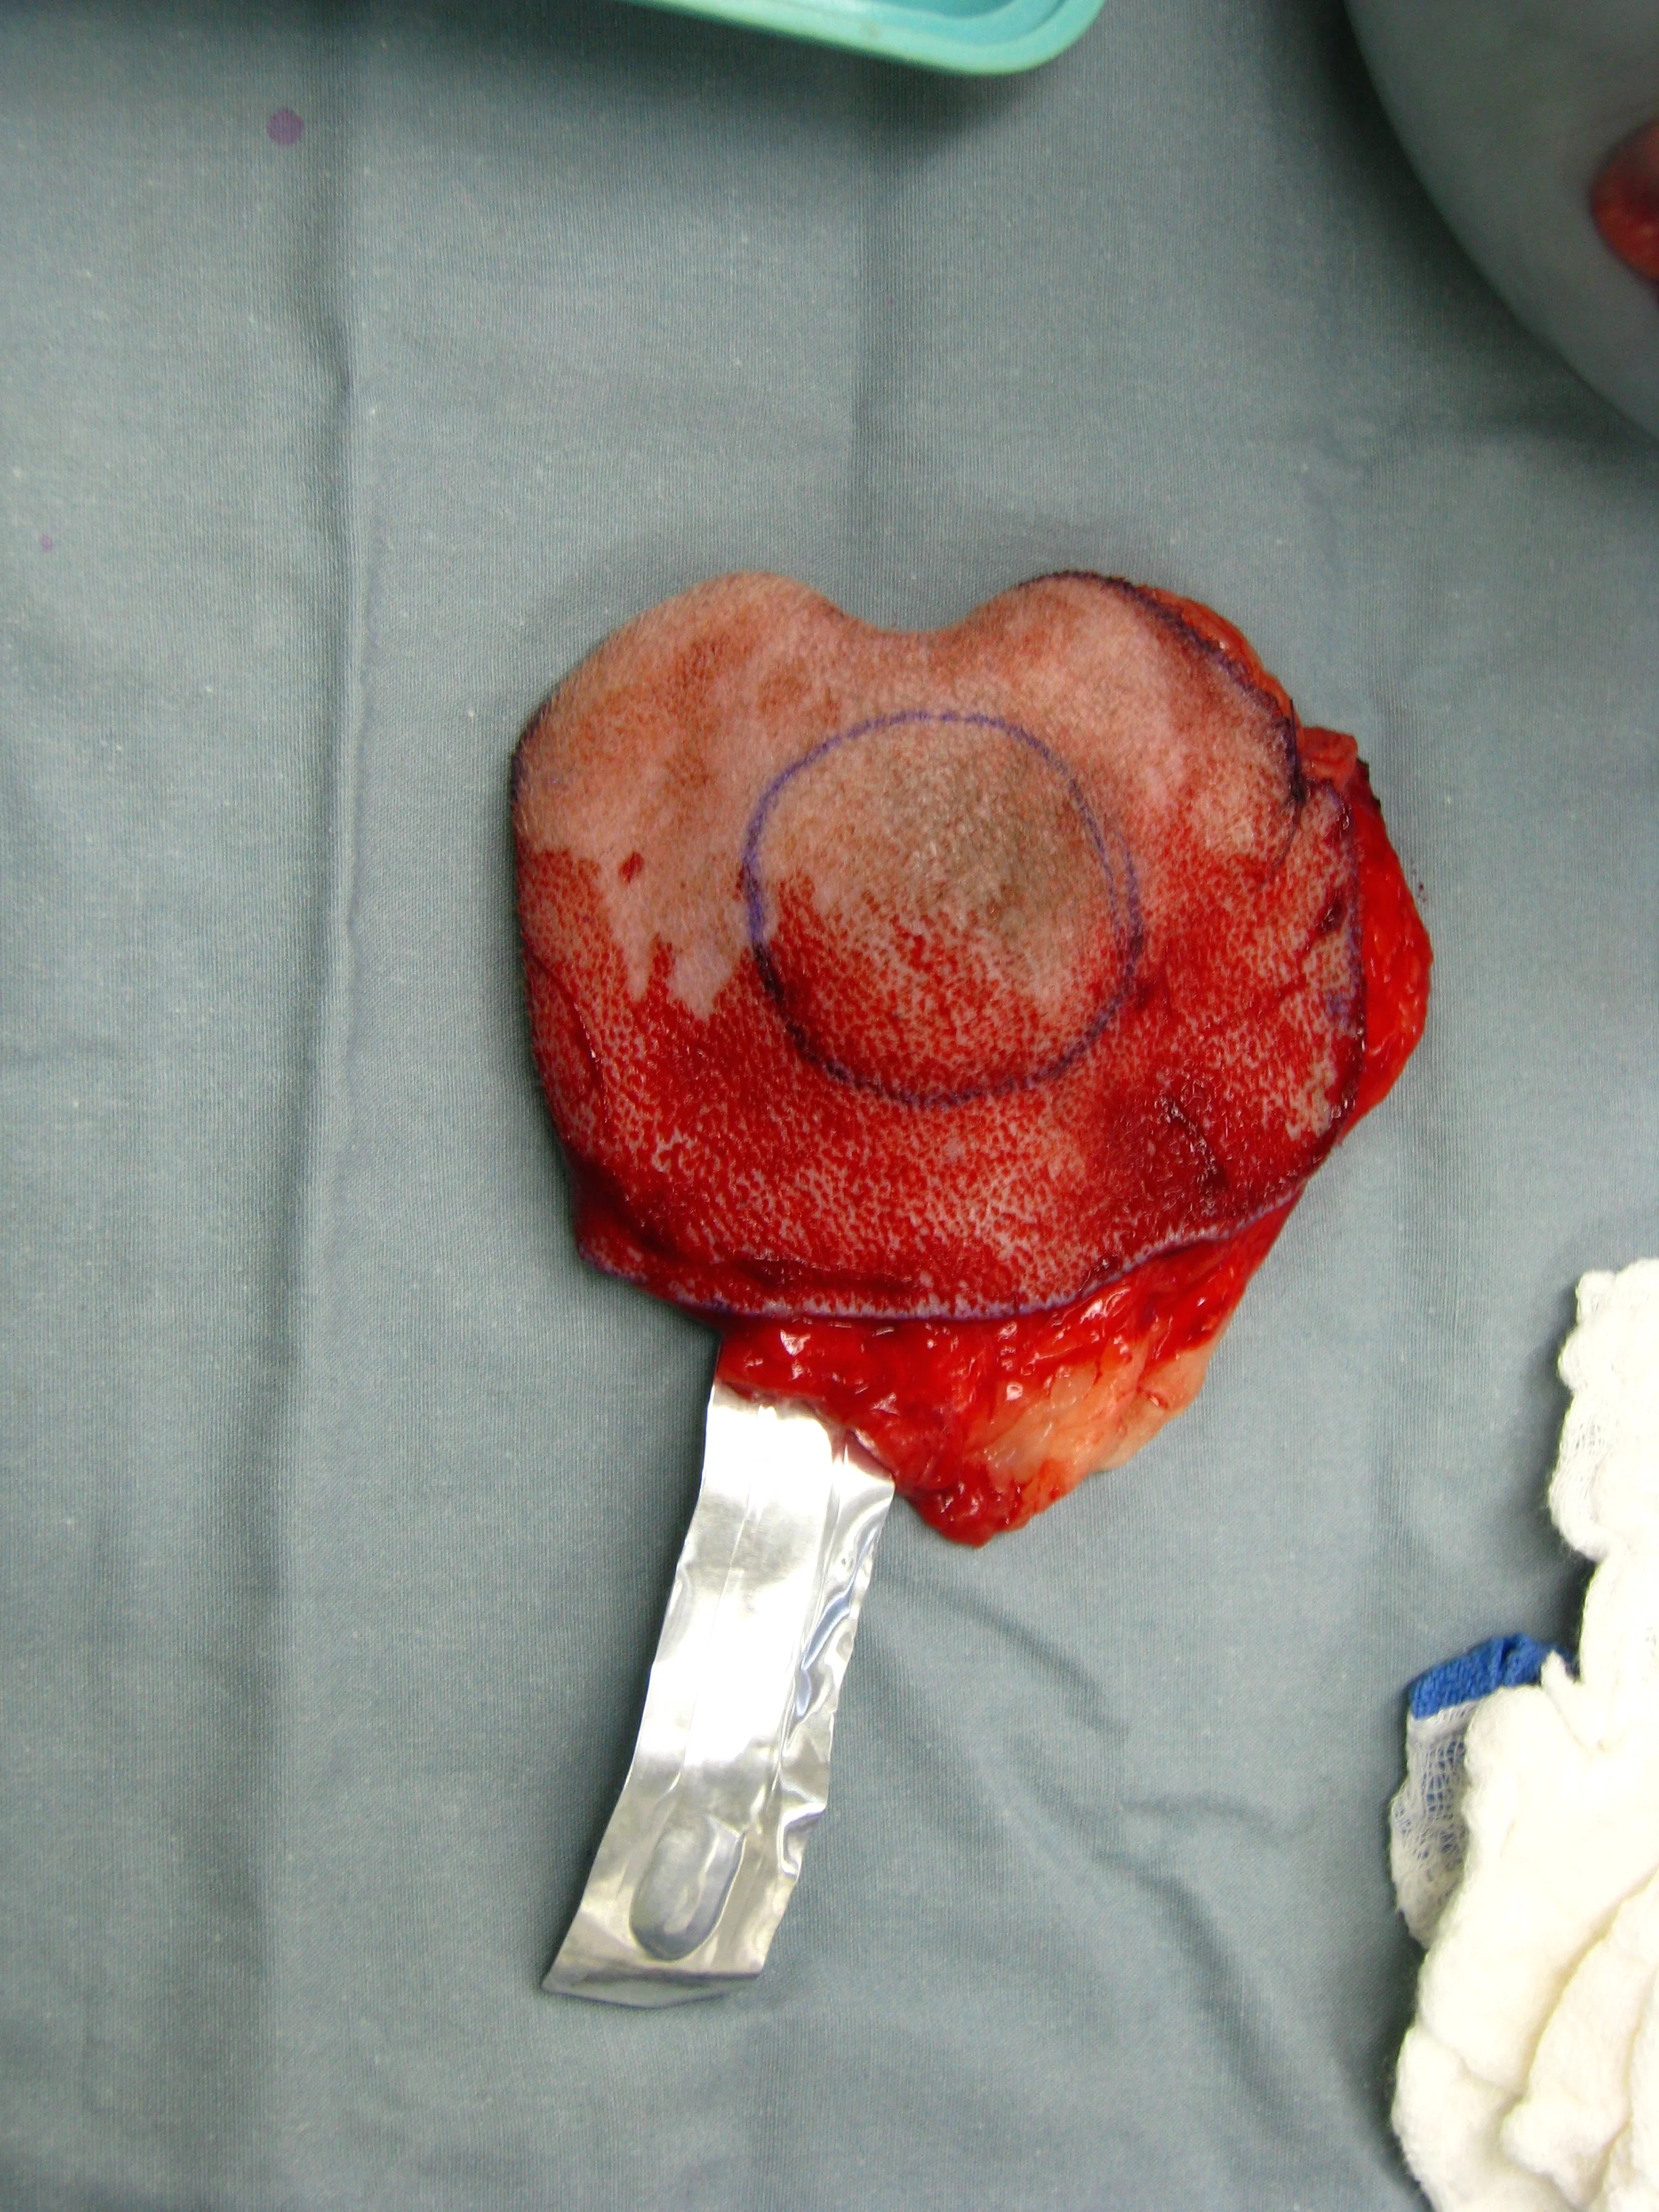

5. Splenic Mass

Splenic masses are commonly treated with splenectomy. In most cases, the tumor type is not known at the time of surgery. In the absence of a hemoabdomen, an ultrasound-guided fine-needle aspirate can be performed to determine tumor type of a solid mass. In cases of cavitated masses, with or without hemoabdomen, aspiration is a low-yield, potentially dangerous test and is not recommended. In the author’s opinion, if a small (<2-cm), noncavitated splenic mass is found as an incidental finding on abdominal ultrasound, close monitoring may be appropriate. Ultrasound should be repeated in a month, and splenectomy should be recommended if the mass is progressive. In most other cases, splenectomy to prevent rupture of the mass and hemoabdomen is recommended. If the patient is presented with a hemoabdomen, the splenectomy is an emergency (Figure 5). Staging should be performed with a minimum of 3-view thoracic radiographs and abdominal ultrasound (or thoracic and abdominal CT scan).

Splenic mass without hemoabdomen